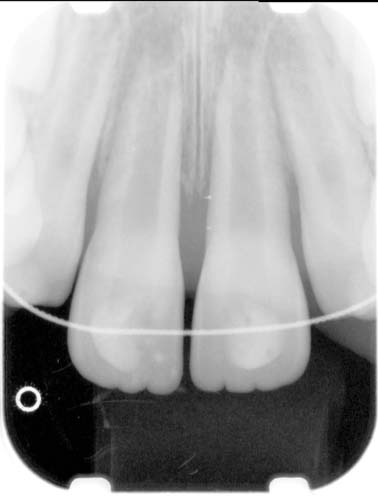

In 2015, a 9-year-old girl presented with a complaint of a bubble on her gums. She had no pain, but she and her mother were concerned because they had been told by their pediatric dentist about an infection. A clinical exam showed a sinus tract that traced to the apex of tooth UR1, which had an incisal edge composite (Figs. 11 and 12). Upon questioning, a history of trauma one or two years previously was reported, with no subsequent symptoms or treatment other than the composite repair.

In contrast to the development of UL1, the pulp in UR1 appears to have become necrotic soon after the trauma. With the wide-open, divergent apex and level of root immaturity, pulp regeneration seemed to be the most desirable option. This was undertaken using diluted sodium hypochlorite and calcium hydroxide medicament at the first visit and 17% ethylenediaminetetraacetic acid (EDTA) at the second visit. The sinus tract healed between visits. A clot was induced and Biodentine from Septodont was used as the material against the scaffold. A composite restoration was eventually placed and the patient was monitored at regular intervals (Fig. 13).

Over the next two or three years, the periapical pathosis healed, which is the first goal for regeneration. However, the second goal of further root development—root wall thickening and closure—did not occur; rather, a radiopaque, hard tissue formation developed both in the apical third of the canal and toward the apical opening (Fig. 14).